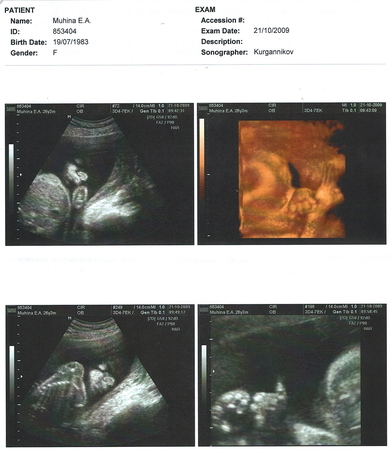

а вот и наши фотки 25 недельки (УЗИ)

Результаты: УЗИ, КТГ, доплера, скрининга25 неделек: слева и верх и низ - вид снизу на наш ШНОП =) т.е. можно увидеть личико, если смотреть (как бы) снизу...справа верх 3D личико, но закрыла наша детка его ручками (ручки скрещены на носике), а на нижнем правом детка нам показала "Класс" (большой палец вверх) только вот немного размыто, но это извиняйте врач так сделал

прикольно) Правда поняла, что там такое только на 3D фотке. На остальных не разглядела, видимо моя фантазия подвела)

=))) я тоже не сразу сфокусировалась =))) на фотках слева, если смотреть снизу и левее, то можно увидеть большой носик снизу (две носопырки видны) губки и закрытые глазки =) ну оч недевольное личико, разбудили её понимаешь ли =))

только пальчики какие-то непонятные...пухлячки =)) я ожидала увидеть пальчики маааааленькие такие, а они видимо ещё не совсем сформировались....или я что-то не понимаю